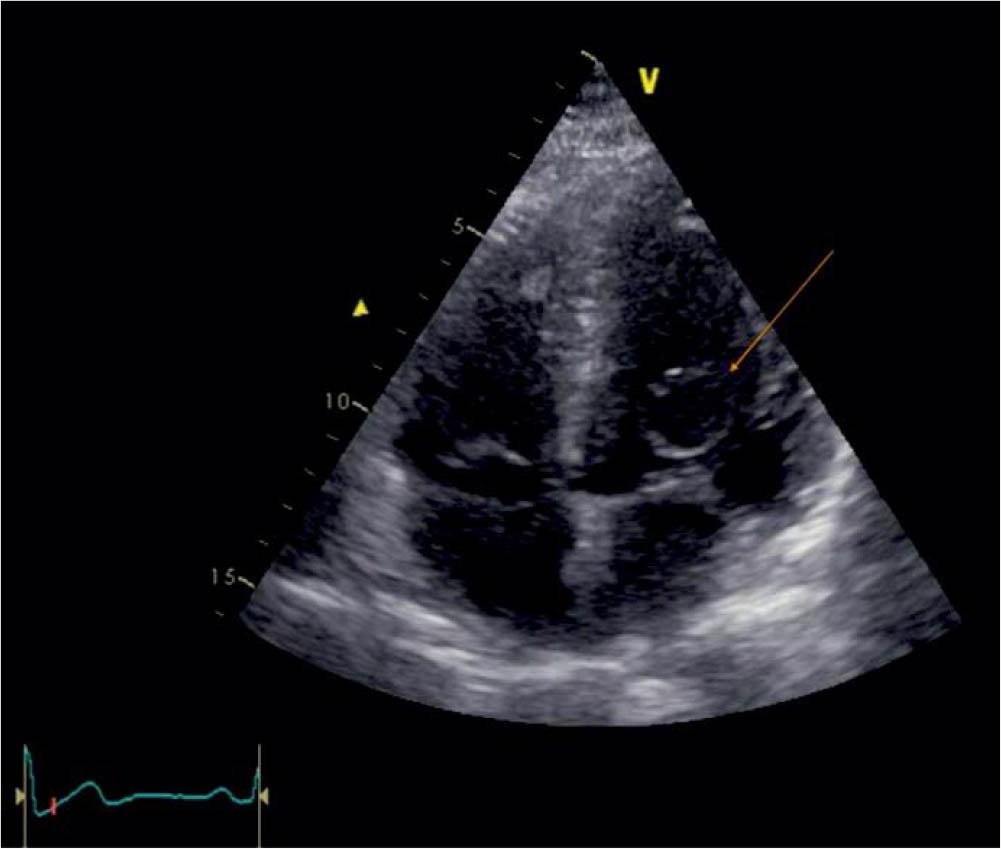

Figure 1